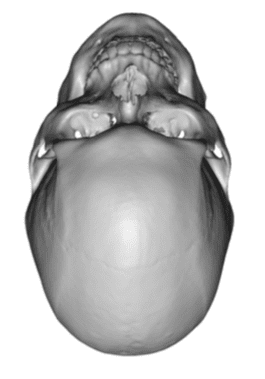

Desire for an improved head shape so that it looks rounder and not so peaked or sloped.

Placement of custom skull implant for parasagittal augmentation to create a rounder head shape. An example of what appears to be a high sagittal crest that is really low parasagittal skull areas.